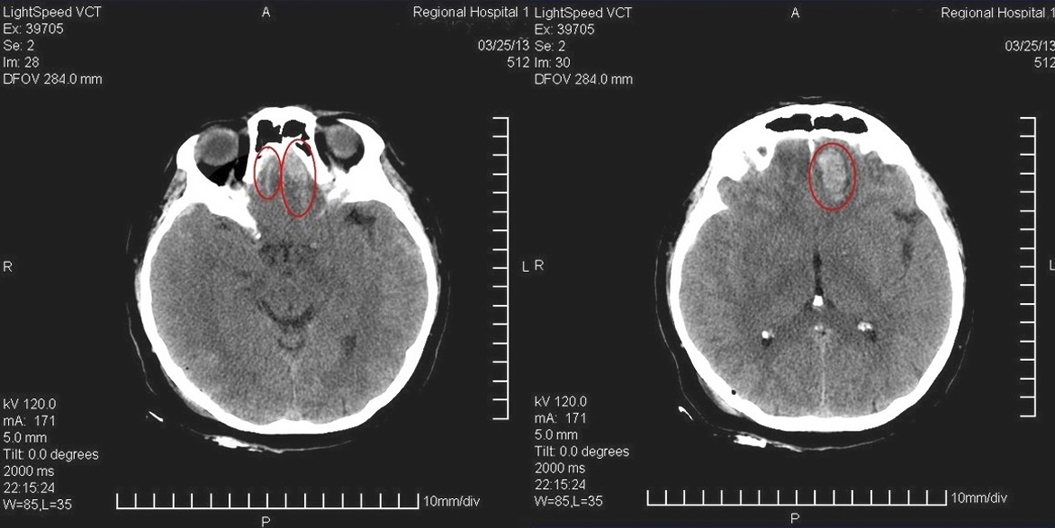

Нельзя обойти вниманием микроконтузионные очаги в лобных долях как еще один вид повреждений, способных возникнуть вторично в результате контрудара.

Рис. 5. Очаги повреждений в результате контрудара в лобных долях.

Для объяснения этого явления наиболее распространена кавитационная теория (A. Gross, 1958), в основе которой лежат законы гидродинамики. Кавитация связана с нарушением непрерывности жидкости и образованием внутри самой себя вакуумных полостей, пустот, с возникновением в них отрицательного давления. Каждая полость формируется из ядра, растет до конечных (критических) размеров, после чего схлопывается. Цикл длится несколько миллисекунд. При схлопывании пузырьков возникает перепад давления, способный достичь 4000 атм, или ~4*10(8) Па (Б. М. Яворский, А. А. Детлаф, 1979).

Рис. 6. Механизм формирования кавитационных пузырьков (F. Unterharnscheidt, J. T. Unterharnscheidt, 2003. Boxing: MedicalAspects).

Силы кавитации настолько велики, что способны вызвать разрушение бетонных конструкций разных гидротехнических сооружений, повредить гребные винты морских судов. Это явление развивается при движении твердых тел в относительно подвижной жидкости, как в замкнутом, так и в незамкнутом объеме. Головной мозг вместе с ликвором и кровью составляет основу содержимого внутри черепа, по относительной плотности они близки друг к другу и имеют значительное содержание воды. Возникновение кавитации в зоне противоудара связано с отрицательным давлением в этой области, которое случается при оттеснении мозга от внутренней поверхности черепа в направлении удара. Наиболее выраженные повреждения при ударе по затылку возникают ближе к границе мозга, то есть в коре лобных долей. Морфологически это разрушение целостности капилляров, мелкие кровоизлияния, гибель клеток коры. Несложно догадаться, к чему приводят такие «воспитательные» воздействия на формирующийся и развивающийся мозг ребенка.